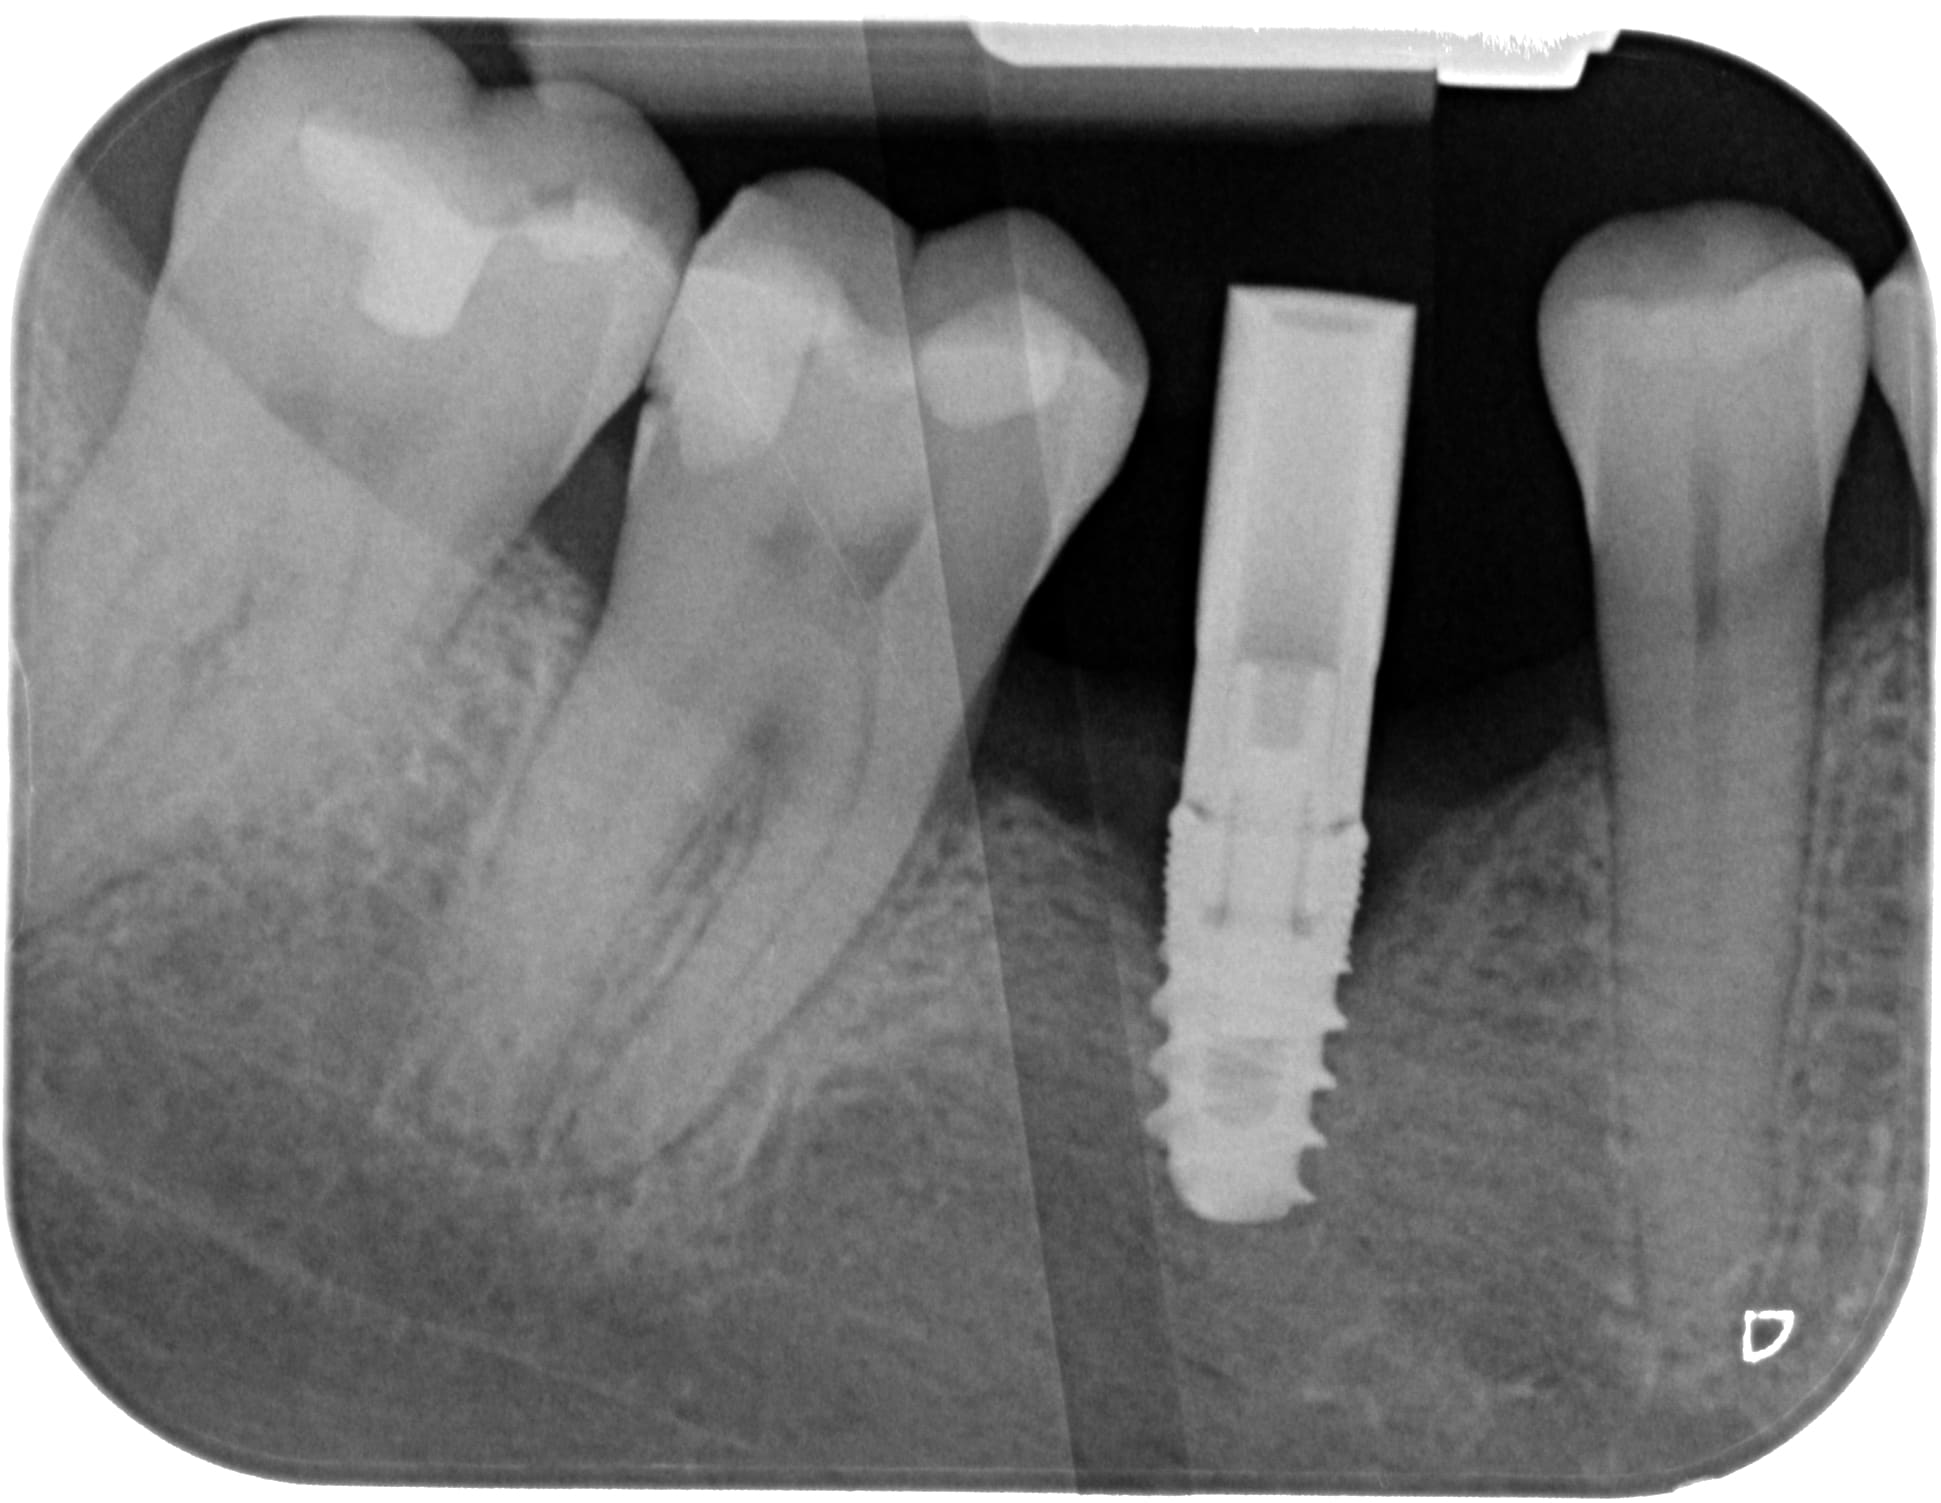

controle à 3 mois post pose d'implant et voilà... perte au niveau des micro-spires ++...

Pourquoi ? la gencive est nickel, RAS niveau santé, compression de l'os? pourtant j'évase la corticale...

On dépose ou pas ? car vraiment gencive RAS? pas de saignement ou autre

l'angle de prise de vue me semble accentuer une perte au col de l'implant qui me parait à la base un manque d'enfouissement. En flapless il est plus délicat de contrôler mais apparemment ce n'est pas cela...

L'implant me semble presenter une plateforme sweatching du coup il fut poser 1mm ou 1,5 en sous crestale ...rien a voir mais pour une 6 la position idéal est a cheval sur septum racine médiale...

Laisse moi deviner ... c’est un ETK?

Raté ! Mis Seven

Je parie que l'os autour du col implantaire était pas suffisant. Tu as dû posé un 4mm dans un os qui fait 6 mm d'épaisseur au sommet.. du coup os pas assez nourri, et donc résorption.. voula mon humble avis.

malheureusement, c'est mort pour cet implant...

donc dépose

pour les causes possibles:

-manque de volume osseux

-compression due à cet implant extrèmement compressif...le seven c'est plutôt un implant pour l'os maxillaire ou os peu dense...et là tu es en mandibulaire...

-échauffement lors du forage

-etc....